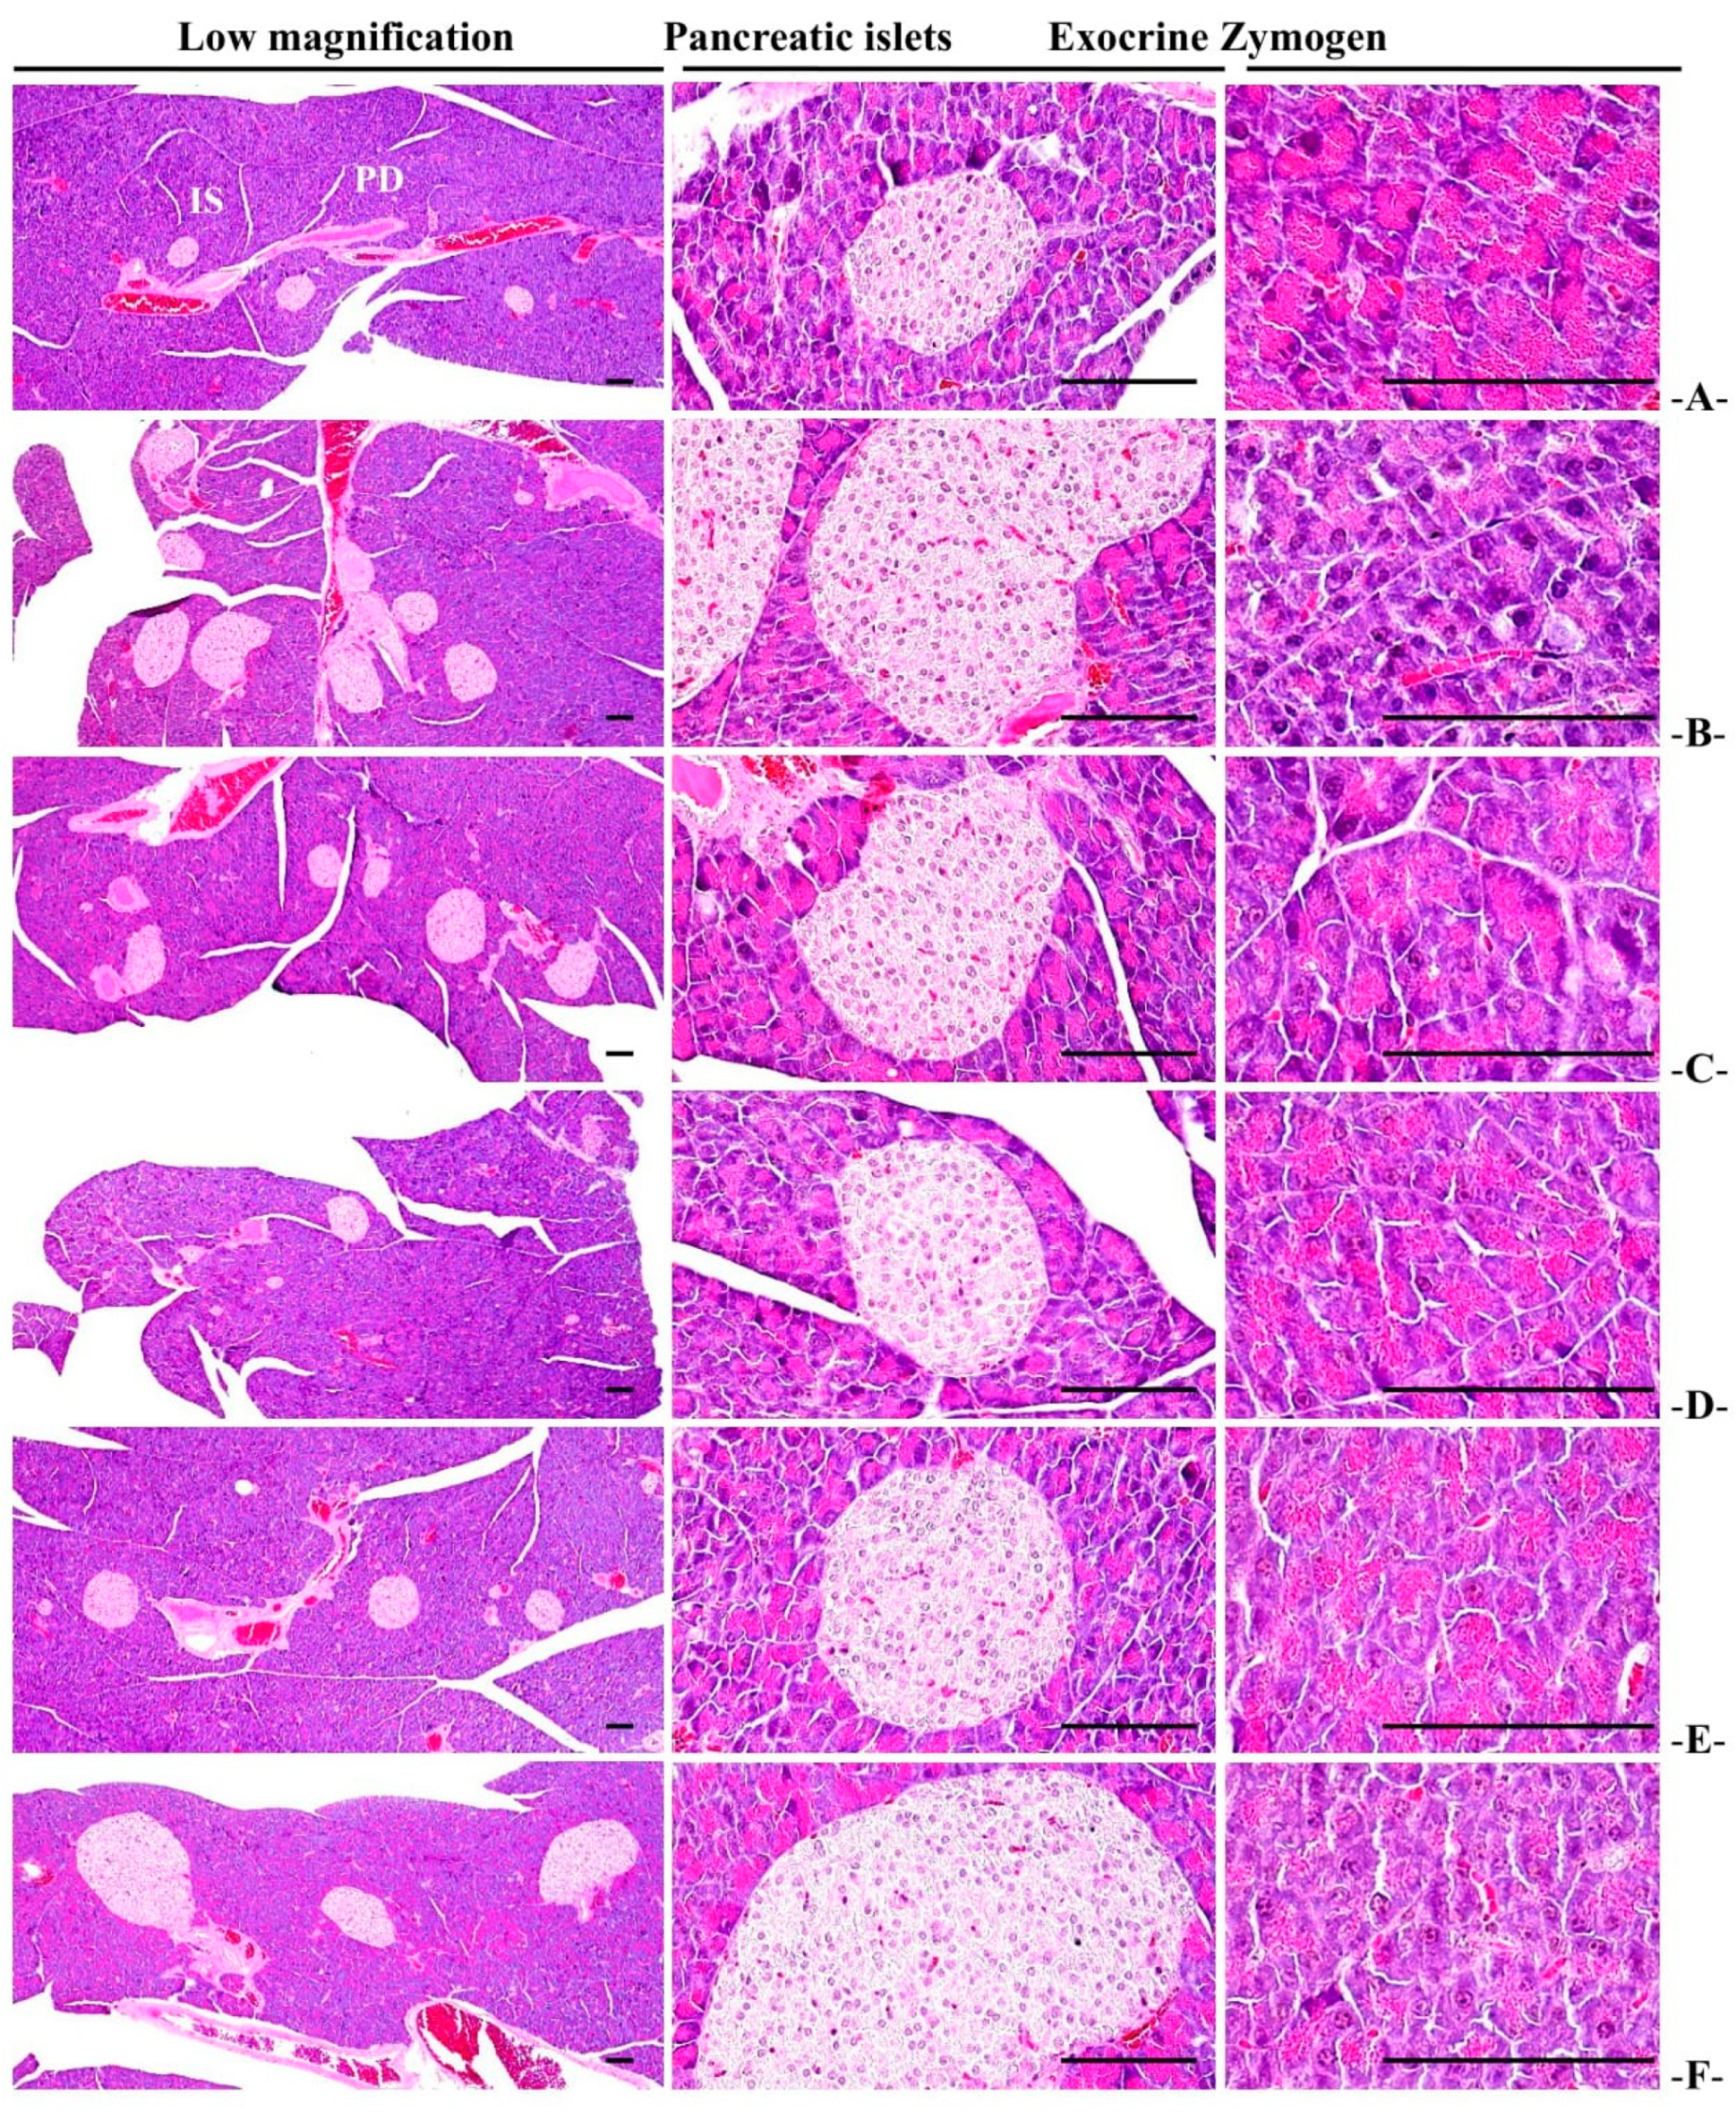

3.2.6. Histopathological Changes of Zymogen Granules in the Exocrine Pancreas

3.3.5. General Histopathological Changes in Pancreatic Islets

| Items Groups | Zymogen Granules (%/mm2 of Exocrine) | Mean Islet Numbers (Numbers/10 mm2) | Mean Islet Diamete (μm/Islet) | Insulin-IR Cells (cells/mm2) (A) | Glucagon-IR Cells (cells/mm2) (B) | Insulin/Glucagon Ratio (A/B) |